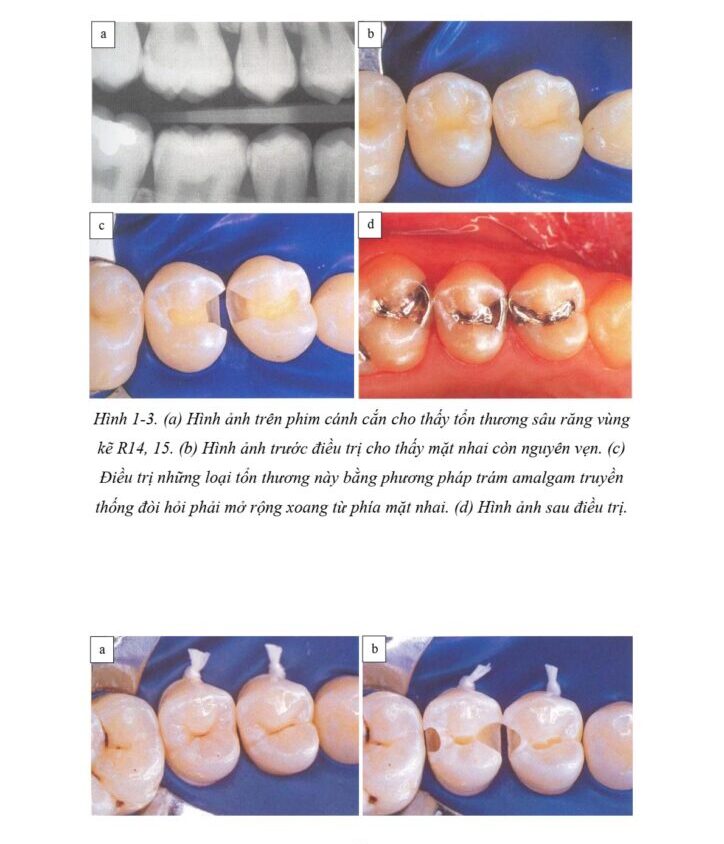

Việc phòng ngừa và cải thiện thói quen vệ sinh răng miệng ngày càng làm giảm đáng kể tỉ lệ mắc các bệnh lý răng miệng và nhu cầu điều trị phục hình. Điều này dần dần đặt ra các câu hỏi về quan điểm điều trị truyền thống và đặt nha khoa phục hồi vào một vị trí trung tâm, tạo ra động lực mới cho các kĩ thuật điều trị bảo tồn hơn (H1-2 đến H1-4).

Hiện nay vẫn không có một loại vật liệu kim loại truyền thống nào đáp ứng một cách thỏa đáng những yêu cầu nói trên. Với amalgam, nứt gãy răng, đổi màu răng đã và vẫn đang là những trở ngại thường gặp (H1-5 đến H1-8).